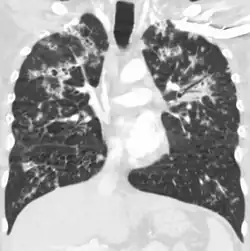

| Seu nome se refere a similaridade dos seus focos de infecção com grãos de milho espalhados pelo pulmão em 90% dos exames de raio-X. | |

A Tuberculose miliar ou tuberculose cutânea aguda disseminada é uma classificação médica internacional para um agravamento da tuberculose por sua ampla difusão dentro do corpo humano gerando pequenas lesões na pele (de 1 a 5mm).[1]